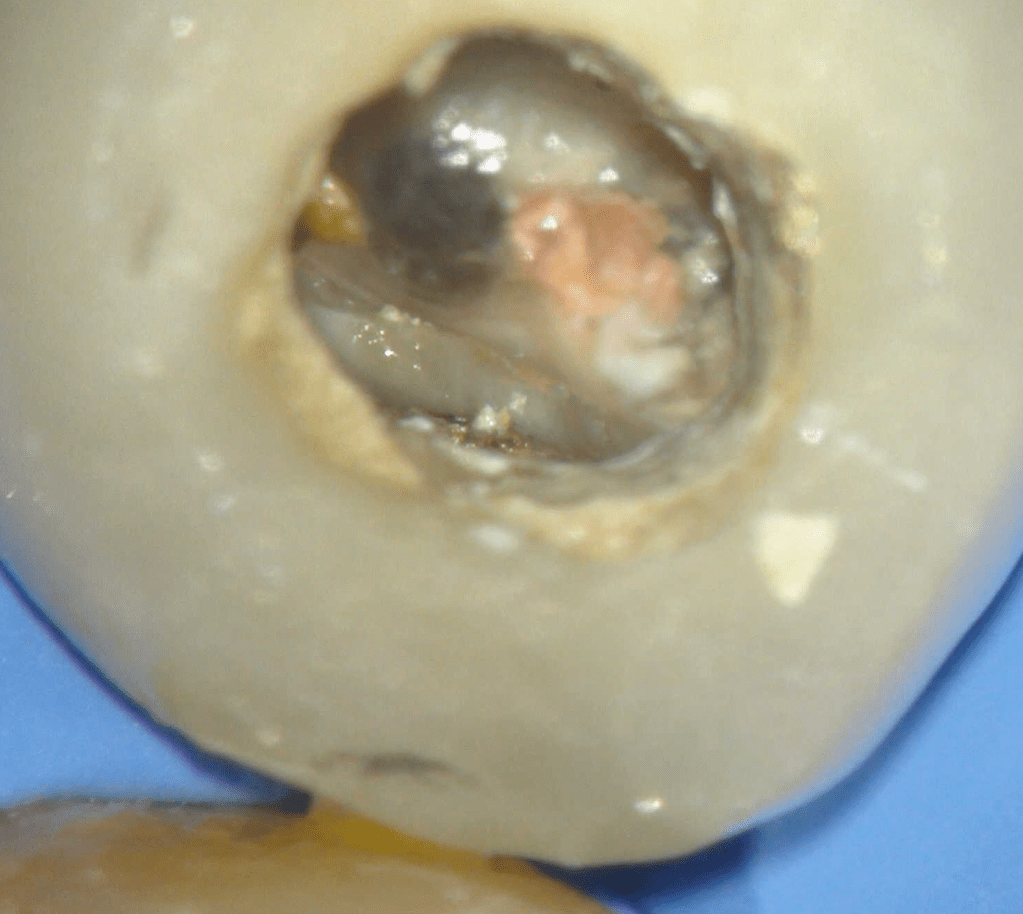

Fisura, remoción amalgama para explorar